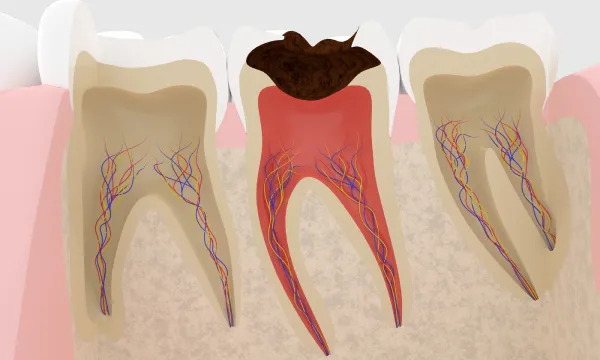

「神経をとりますね。」この言葉、驚きませんか?いくらひどい腰痛でも神経をとって治すことはしません。なぜ歯科だけに神経をとる治療があるのでしょうか?その答えは「歯の中」という特殊な環境にあります。 基本的には歯の中の神経以外の部分には血管はありません。 つまり新陳代謝が行われているのは神経のみ、ほかの部分は変化しない部分と言えます。 この神経の中の血管は非常に細く、虫歯などで炎症がおこると充血して血行不良になり容易に死んでしまうのです。 根の治療とは、死んだ組織、または回復が望めないほど炎症がある神経を取り除き、周りに広がった炎症の原因になる 腐敗物をきれいにして、炎症が起きづらい様に、空いた空間に無菌的にゴムを詰め込む治療のことです。

歯の中の神経は曲がりくねって、また枝分かれすることも少なくありません。それを歯の上から手探りで掃除するかなり 難易度の高い治療です。そのため、再治療の頻度も比較的高いといえます。また新陳代謝の無くなった歯は、枯れ木 のようにもろくなる傾向にあります。さらに、失った歯の部分を補うため土台を立てる必要があり、維持のために金属の杭を 使うことがありますが、この杭のクサビ作用によって、歯が縦割れしてしまう問題もあります。 当院では、この問題を解消するため、グラスファイバーの土台も選択可能ですが、いずれにしてもリスクを伴う治療ということが 言えます。

神経を取らない努力

炎症が神経にまで及ぶと、一般的には痛みが起こり神経に炎症が波及し根の治療になることが多いです。しかし、神経に炎症が波及しても、神経すべての部位で細菌が広がり、炎症が起こり神経が死んでしまうわけではありません。 神経にも炎症に対する抵抗力があり、それ以下の炎症ならば生き抜くことも十分考えられます。つまり、回復が望めない部位のみ神経を取り除き、それ以下の神経は回復を期待して残すという考え方です。 そこで、当院ではマイクロスコープを駆使し、神経の切断面と出血の状態を観察することによって神経の状態を観察し、生き残ると思われる部分から先の神経を残すことを行っています。

う蝕が深く、不幸にして神経をとらなければならなくなった場合と、根の治療のやり直しになった場合の手順を説明したいと思います。

神経をとる治療

不幸にして神経をとらなければならなくなった場合は、神経が回復不可能、つまり死ぬ方向に進んでしまった場合に行います。まず、健全な歯の部分はなるべく削らず、更に根の治療が効率的に出来るように形成します。すると神経の上の部分がまず露出します。この部分は髄室といいます。 この部分の神経をしっかりとれるように角の部分(髄角)までしっかり形を作ります。その後、その下にある根の部分の神経の入り口(根管口)を探します。歯の種類に種類によって大まかな数は決まっていますが実際にはそれより多いことが多いので顕微鏡を使って慎重に探索し、取り残しのない様にします。 根管口が見つかったら神経を根の先まで探索し神経を除去します。神経はまっすぐなことはないので、途中で曲がった道に追従できずに進まなくなったり、また誤って別の道を作ったりしないように慎重に行います。